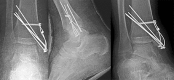

Case summary: We report a very rare injury of closed TTD with a follow-up period of 36 mo. Initial closed reduction was not successful because of a fractured highly unstable medial malleolus displaced into the ankle mortise, blocking the relocation of the talus. The patient was able to walk pain-free after the 3rd month of surgery. At the 36-mo follow-up, there were 10 degrees of flexion loss and 10 degrees of extension loss in the tibiotalar joint. Furthermore, 5 degrees of subtalar joint inversion-eversion loss was present.